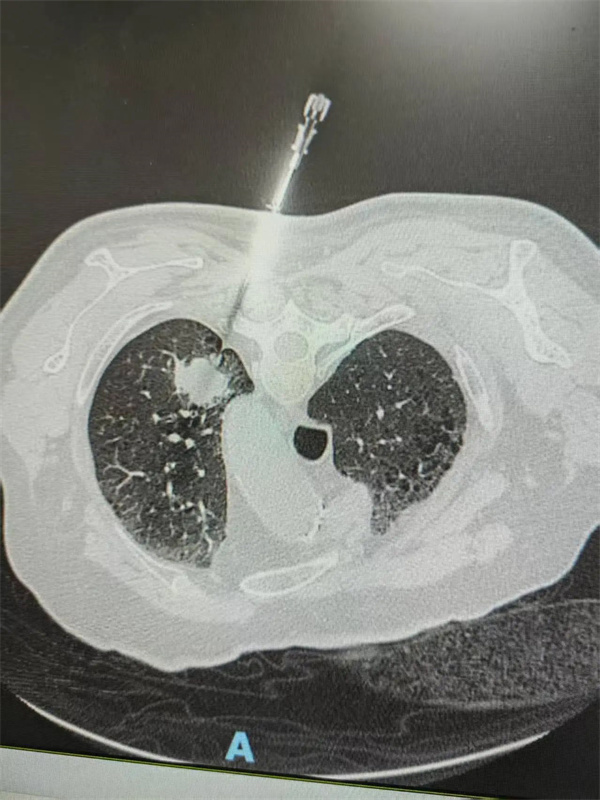

肺部结节CT引导下病灶活检检查术则由呼吸内科刘前桂主任执刀,他凭借深厚的专业功底,为患者诊断提供了有力支持。

以河北涉县患者崔XX为例,患者在当地医院发现肺部结节3个月,大小6mmX8mm,疑似肿瘤。得知北京老年医院呼吸内科在肺部结节诊疗方面经验丰富,患者及家属慕名前来。刘前桂主任详细了解病情、查看胸部CT后,迅速组织多学科团队会诊,邀请胸外科邓学峰主任、原放射科程钢主任医师共同参与。经深入讨论,团队决定为患者实施CT引导下肺结节穿刺活检,患者继而得以明确诊断,并得到及时有效的治疗。